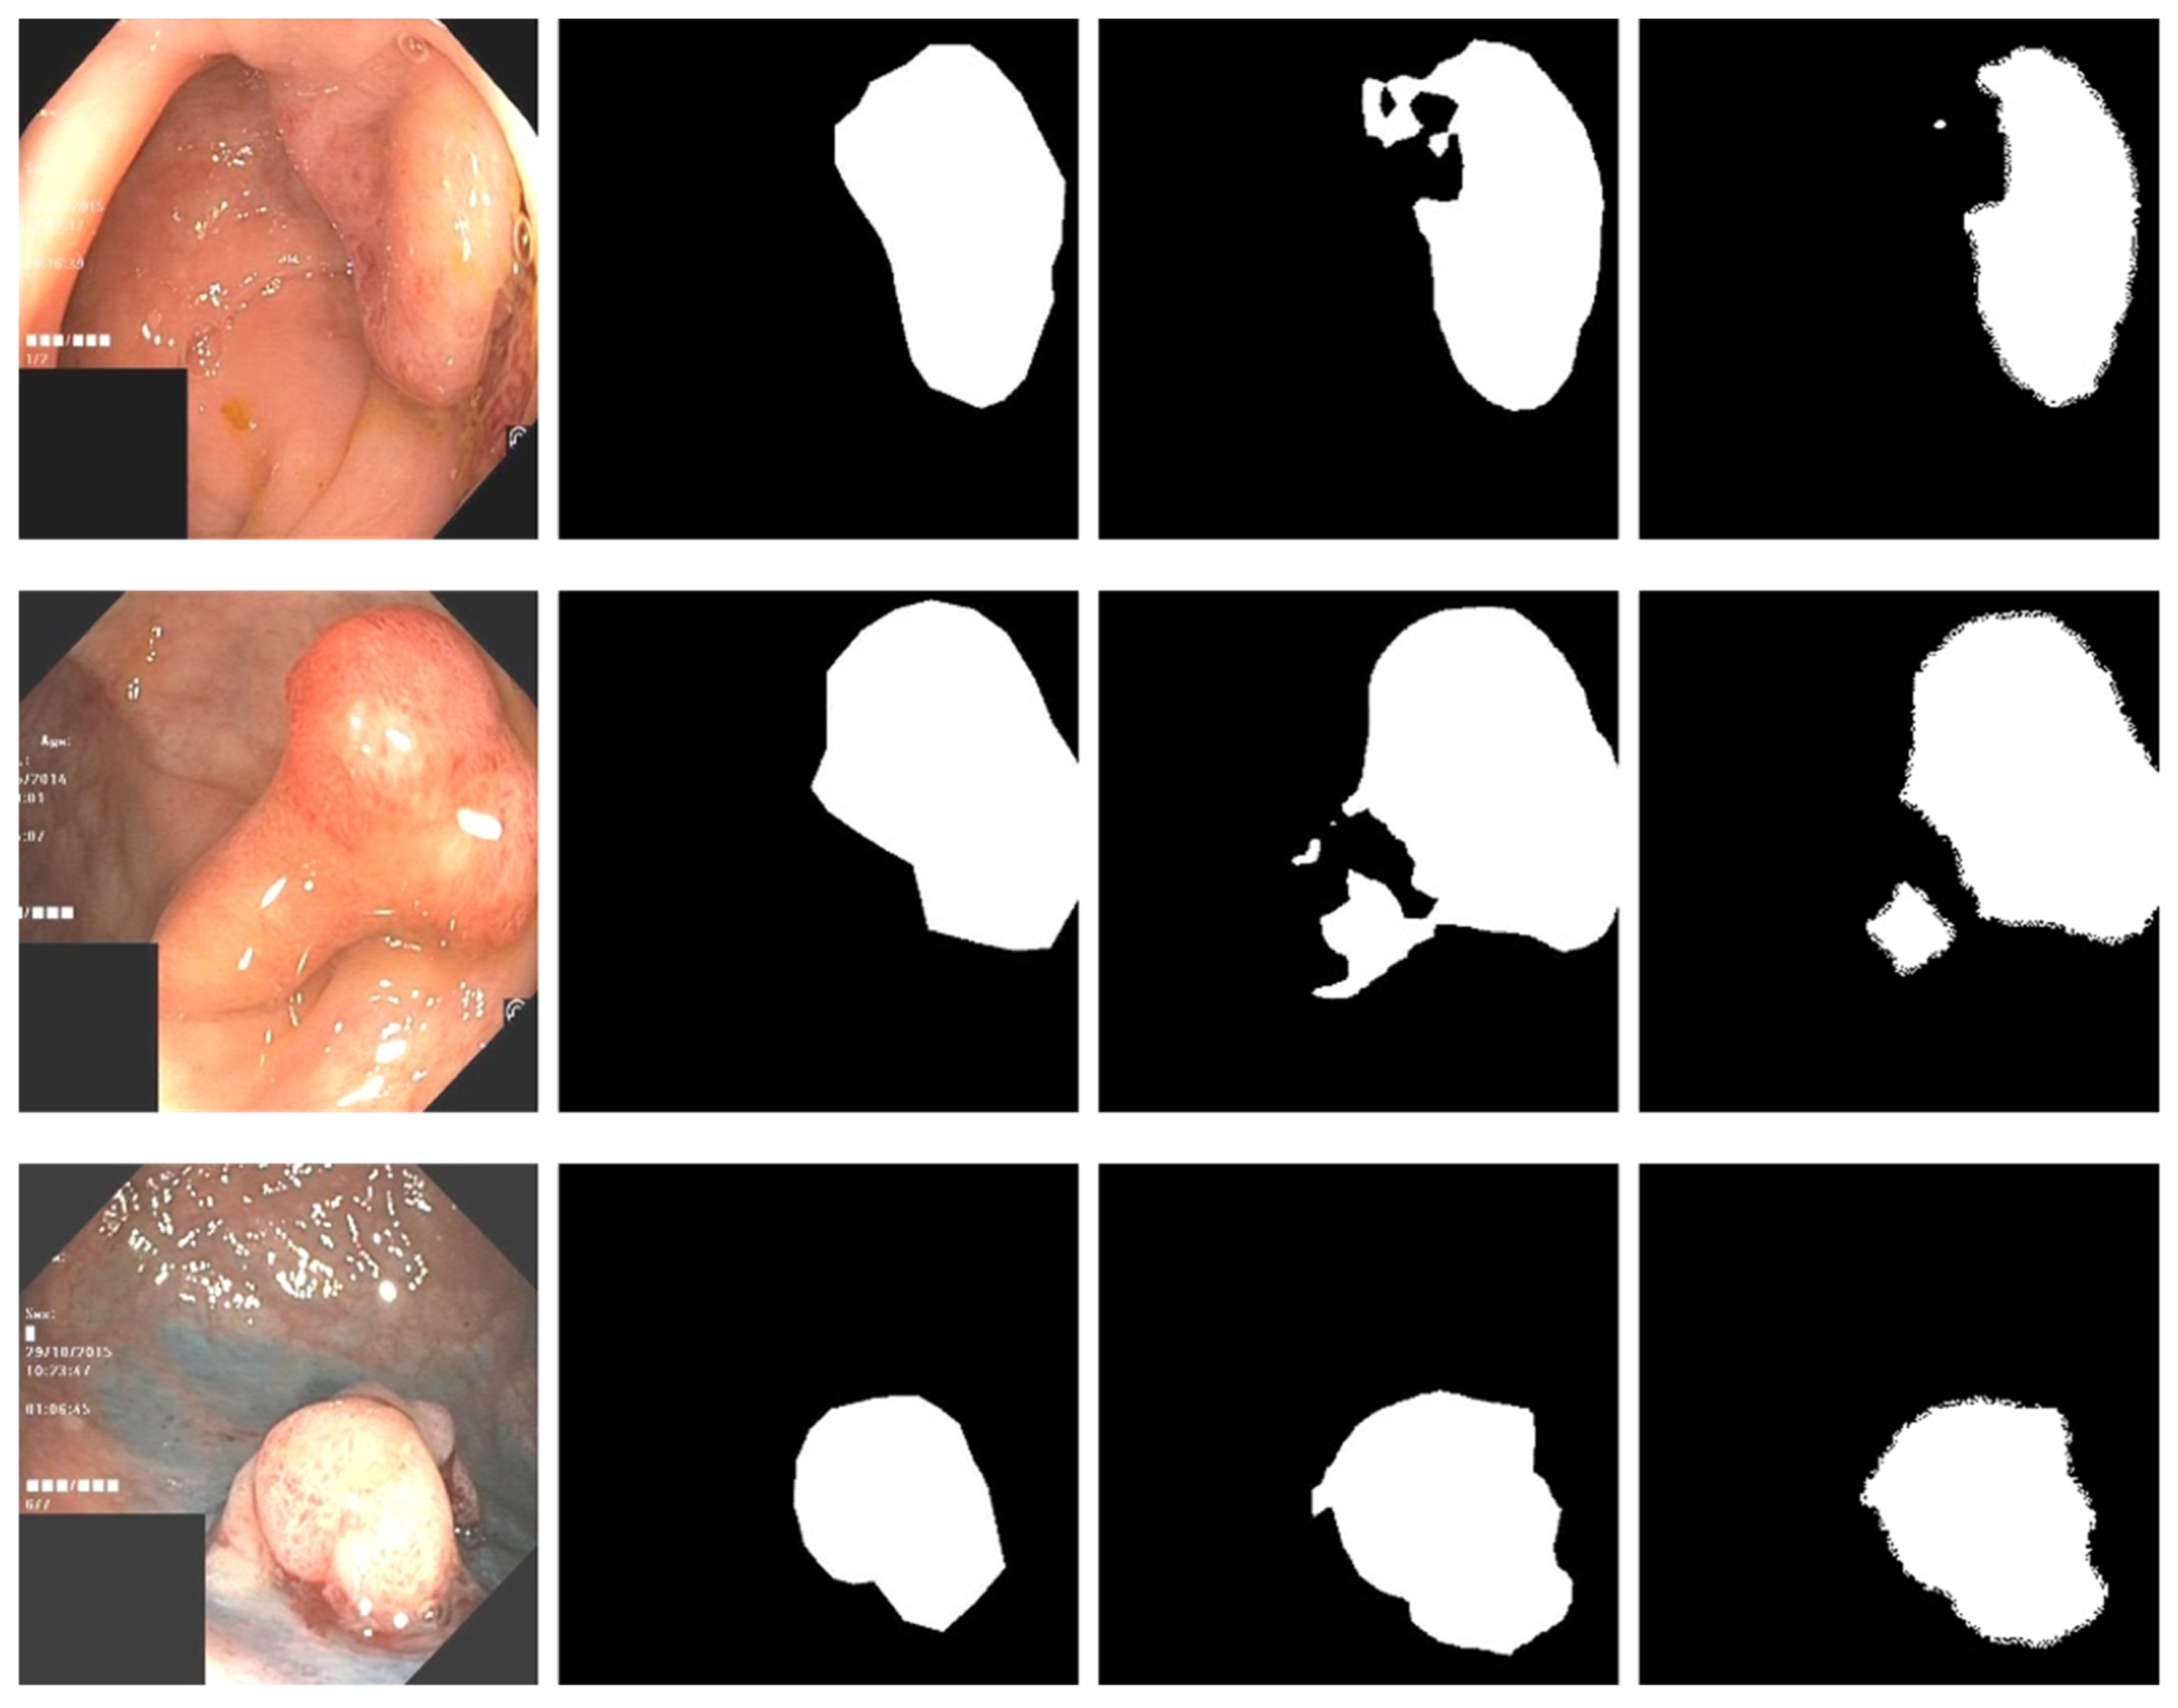

Figure 5 is a comparison of the direct prediction map of the model and the conditional random field after refining the boundary. A conditional random field can effectively fine-tune the boundary of a segmented image. In our work, a high-density conditional random field was applied to the experiment.

Figure 5.

The first column is the original input image, the second column is the mask map, the third column is the direct prediction map of the model, and the fourth column is the prediction map with the conditional random field added.